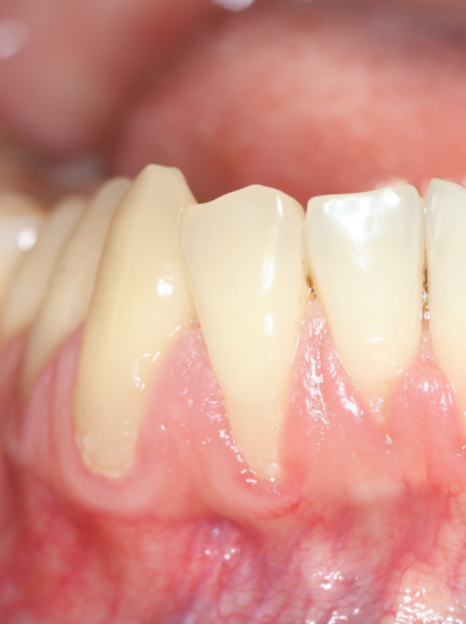

스케일링을 직접 도와드리기 위해

구강 내부를 자세히 촬영해보니

실제로 하악의 치아에 잇몸 퇴축이

발생한 것을 확인할 수 있었어요.